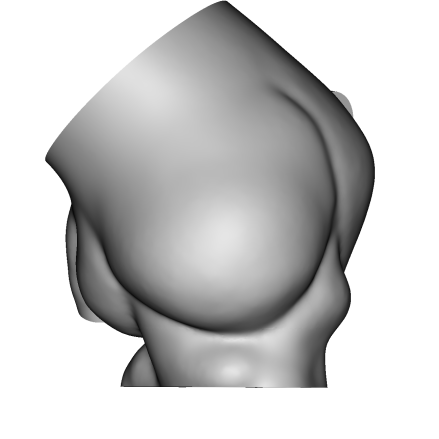

个性化3D打印模型:

3D打印体外模拟:

体外模拟植入29mmJ-Valve瓣膜,升主动脉侧(左图)观察可见定位键挂于无冠瓣上导致瓣架无法到达瓣环位置,左室流出道侧(右图)观察可见瓣架底端距离瓣环平面18mm,且J-Valve在瓦氏窦中呈倾斜状态。